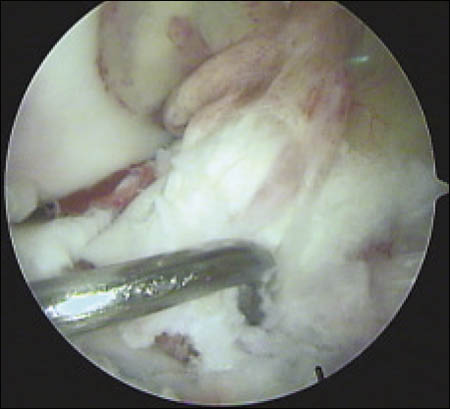

Se realiza un mini abordaje anterior de rodilla 2 cm proximal al polo inferior de la rótula y 3 cm distal al mismo, luego se realiza la esqueletización del polo patelar distal cruentándolo a la demanda. Mediante dicho gesto se reconoce la superficie ósea permitiendo la implantación precisa de los arpones, centralizándolos en plena masa esquelética, se colocan en forma paralela 2 anclajes óseos de 3.5 mm (Arthrex). (Fig. 3 y 4)

Figura 3: Visión intraoperatoria de la lesión del tendón patelar, colocación de 2 arpones paralelos

Cada anclaje posee 2 hebras de sutura Fiber-Wire. La primera hebra de sutura que sale del arpón es pasada mediante puntos de Krackow por el extremo proximal del tendón lesionado y a continuación por el remanente tendinoso adherido a la patela, capturando el tendón a lo largo de su línea media. La segunda hebra de cada arpón es pasada en la parte lateral por el primer arpón y la parte medial del tendón por el segundo arpón, para luego realizar el anudado simultáneo de ambos a nivel del polo inferior patelar. (Fig. 5) Luego las lesiones del retináculo medial y lateral son reparadas con Vicryl 1.

Figura 5: Tendón rotuliano reinsertado